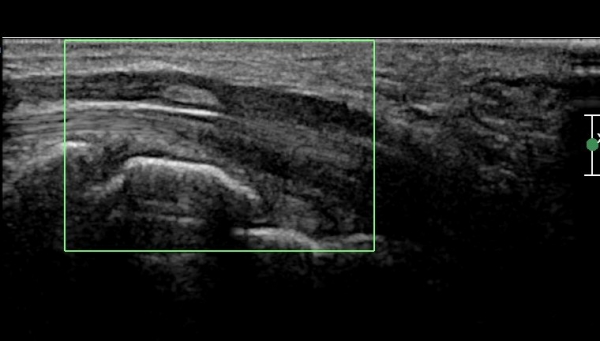

ÃÊÀ½ÆÄ °Ë»ç :  ¼Õ¸ñ¿¡¼­ Á¤Á߽Űæ Ⱦ´Ü¸é°Ë»ç»ó Á¤Á߽Ű泻 °í¿¡ÄÚ Á¾±«°¡ °üÂûµÈ´Ù(»çÁø 1)